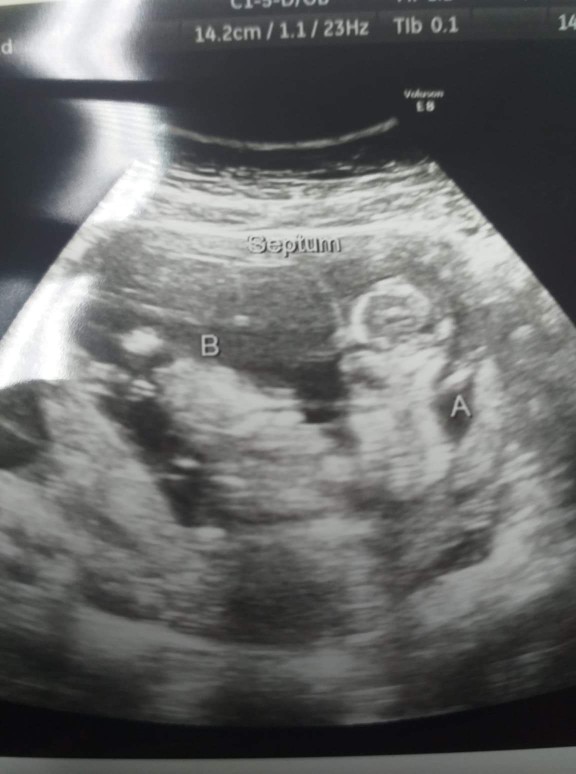

12w. มีติ่งจู๋โผล่ หมอบอกว่ามีโอกาสหดกลับได้ ยังไม่ยืนยันผช.100% แม่ๆคนไหนเจอแบบนี้แล้วกลายเป็นผญ.มั้ยคะ? #จะญ./ช.แม่ก็รัก